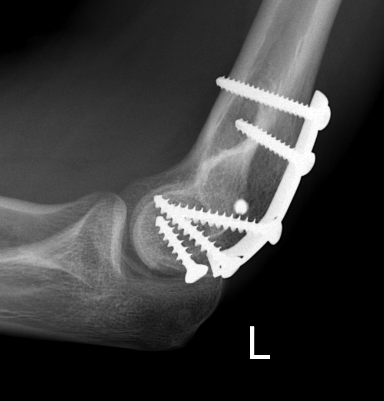

ORIF with PA screws and posterolateral plate

capcapcap

Large capitellum fracture / lateral column ORIF with plate and screws